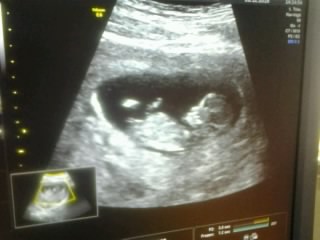

1 марта сходили с мужем на второй скрининг. Очень ждали этого момента) Нашего папу не пустили и ему пришлось ждать в коридоре. А когда я вышла к нему, узнав тайну, он сразу угадал. Сказал что это сын. Потом рассказал что чувствовал это с самого начало, и...

Меня всё волнует вопрос пола ребенка, как и почти всех будущих мам)